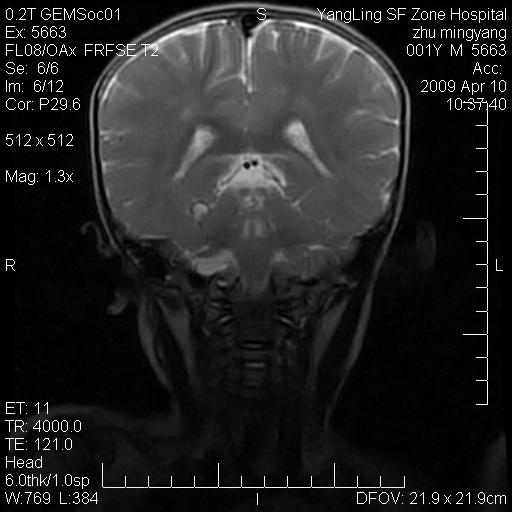

患者:1岁半,两天前外伤收住我院,ct检查小脑占位

考虑星形细胞瘤,建议增强

髓母细胞瘤或血管母细胞瘤,增强后可以鉴别;影像资料见 <。鱼博浪老师的《中枢神经系统ct与mr鉴别诊断》 小脑部肿瘤章节。

髓母细胞瘤或血管母细胞瘤!支持!

支持考虑髓母细胞瘤

考虑----髓母细胞瘤可能性大

考虑髓母细胞瘤或室管膜瘤。

支持髓母细胞瘤。

考虑髓母细胞瘤。

考虑髓母细胞瘤或星形细胞瘤

考虑髓母细胞瘤.

考虑髓母细胞瘤可能性大。

小脑肿瘤.考虑髓母细胞瘤可能.

就病灶部位及临床资料首先考虑髓母.